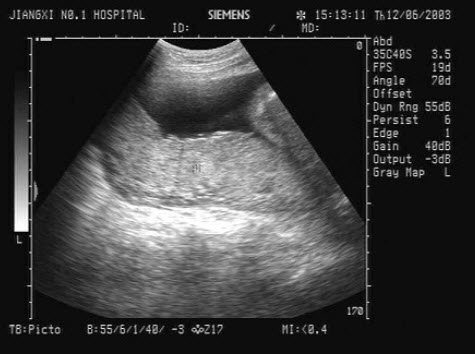

3、单项选择题

男,18岁,外伤1小时就诊。结合超声声像图,诊断为()